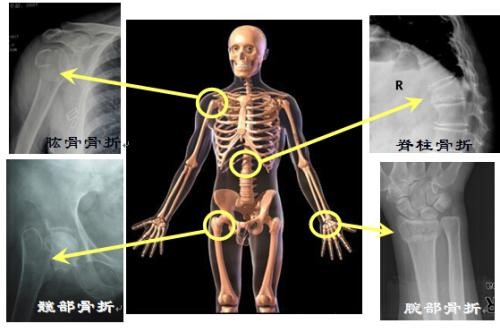

三、骨质疏松性骨折常见部位有哪些?

常见的骨折部位是脊柱、髋部、桡骨远端和肱骨近端,其他部位也可发生。